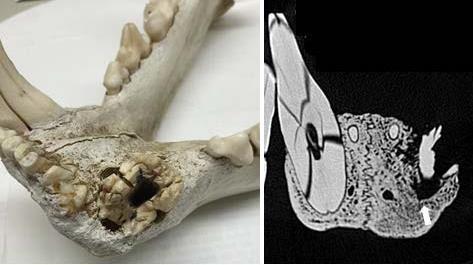

1965年肯尼亚臭名昭著的另1食人狮FMNH 213656,同样与豪猪脱不开关系。尸检发现一根长29.6mm,直径7.4mm的豪猪刺牢牢插入左下犬齿牙髓腔内,之后在压力下豪猪棘刺破裂,伤势扩大,牙龈脓肿。显然这2只食人狮要么被豪猪所伤,要么吃了豪猪。

肯尼亚食人狮FMNH213656的下颚前部与CT扫描的冠状断面,显示犬齿牙龈被豪猪所伤